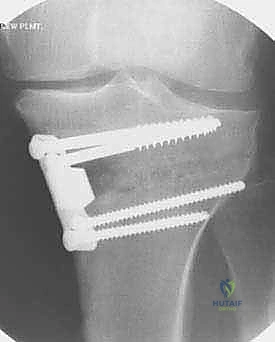

خطوات الجراحة: رحلة دقيقة داخل غرفة العمليات

تُجرى عملية قطع عظم الظنبوب القاصي تحت التخدير النصفي أو الكلي، وتستغرق عادة من ساعة إلى ساعتين. إليك التفاصيل الدقيقة لما يحدث داخل غرفة العمليات تحت إشراف الأستاذ الدكتور محمد هطيف:

3. إجراء القطع العظمي (The Osteotomy):

باستخدام أدوات دقيقة ومناشير جراحية متطورة، يتم عمل قطع غير مكتمل في عظمة الساق. هناك طريقتان رئيسيتان:

* الشق المفتوح (Opening Wedge): يتم فتح العظم من الداخل وإضافة طعم عظمي (صناعي أو طبيعي) لملء الفراغ وتعديل الزاوية. وهي الطريقة الأكثر شيوعاً حالياً.

* الشق المغلق (Closing Wedge): يتم إزالة إسفين (مثلث) صغير من العظم من الجهة الخارجية وإغلاق الفراغ.

4. تعديل المحور:

يتم فتح العظم تدريجياً وببطء شديد حتى الوصول إلى الزاوية التي تم حسابها في التخطيط الرقمي قبل الجراحة.